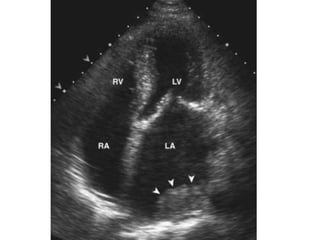

Parachute Mitral valve

Parachute mitral valve: single papillary muscle to which chordae to

both leaflets attach;results in mitral stenosis or mitral regurgitation

Mitral Stenosis etiology 1.Rheumatic: most common cause 2. Severe mitral annular calcification (MAC) 3. Congenital Parachute mitral valve: single papillary muscle to which chordae to both leaflets attach;results in mitral stenosis or mitral regurgitation Supravalvular mitral ring 4. Systemic diseases: can cause valvular fibrosis Carcinoid SLE RA Healed endocarditis